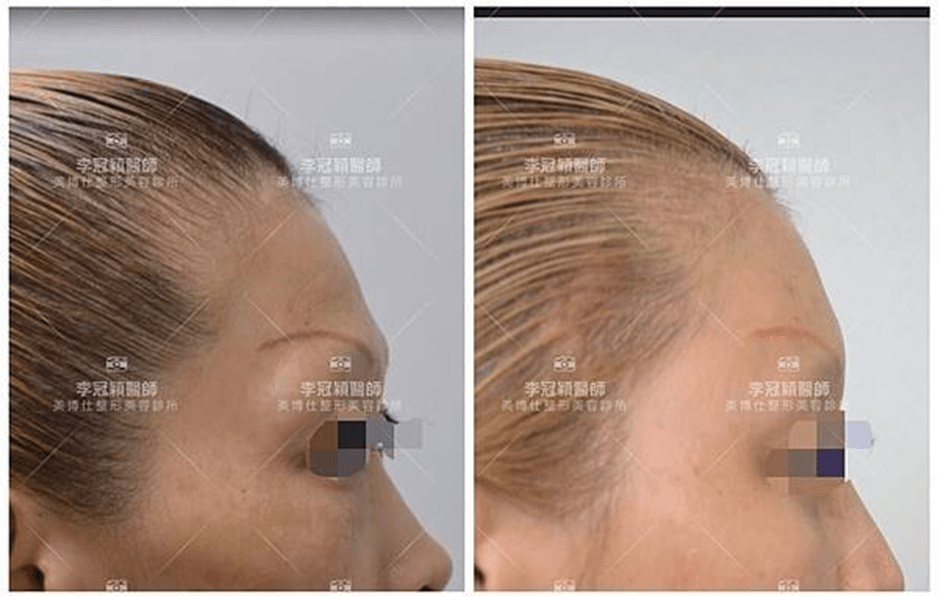

前 後(三個月)太陽穴到側額凹陷,眼尾下垂。(太陽穴不對稱往往來自顴骨大小不對稱)可以調整改善對稱性。

臉型不對稱 在太陽穴有一定落差,上圖經過太陽穴墊片矯正後,也明顯改善不對稱的視覺效果。重要的一點可以支撐眼尾下垂,改善老態眼神!(上圖)經內視鏡墊太陽穴跟提眼尾術後滿意。

(下圖)凹陷太陽穴,提前老態與眼尾下垂,經李醫師內視鏡太陽穴墊片支撐眼尾,幾乎不鬆垂完全抗老。

下圖:太陽穴墊片後兩年,眼尾支撐效果持久。